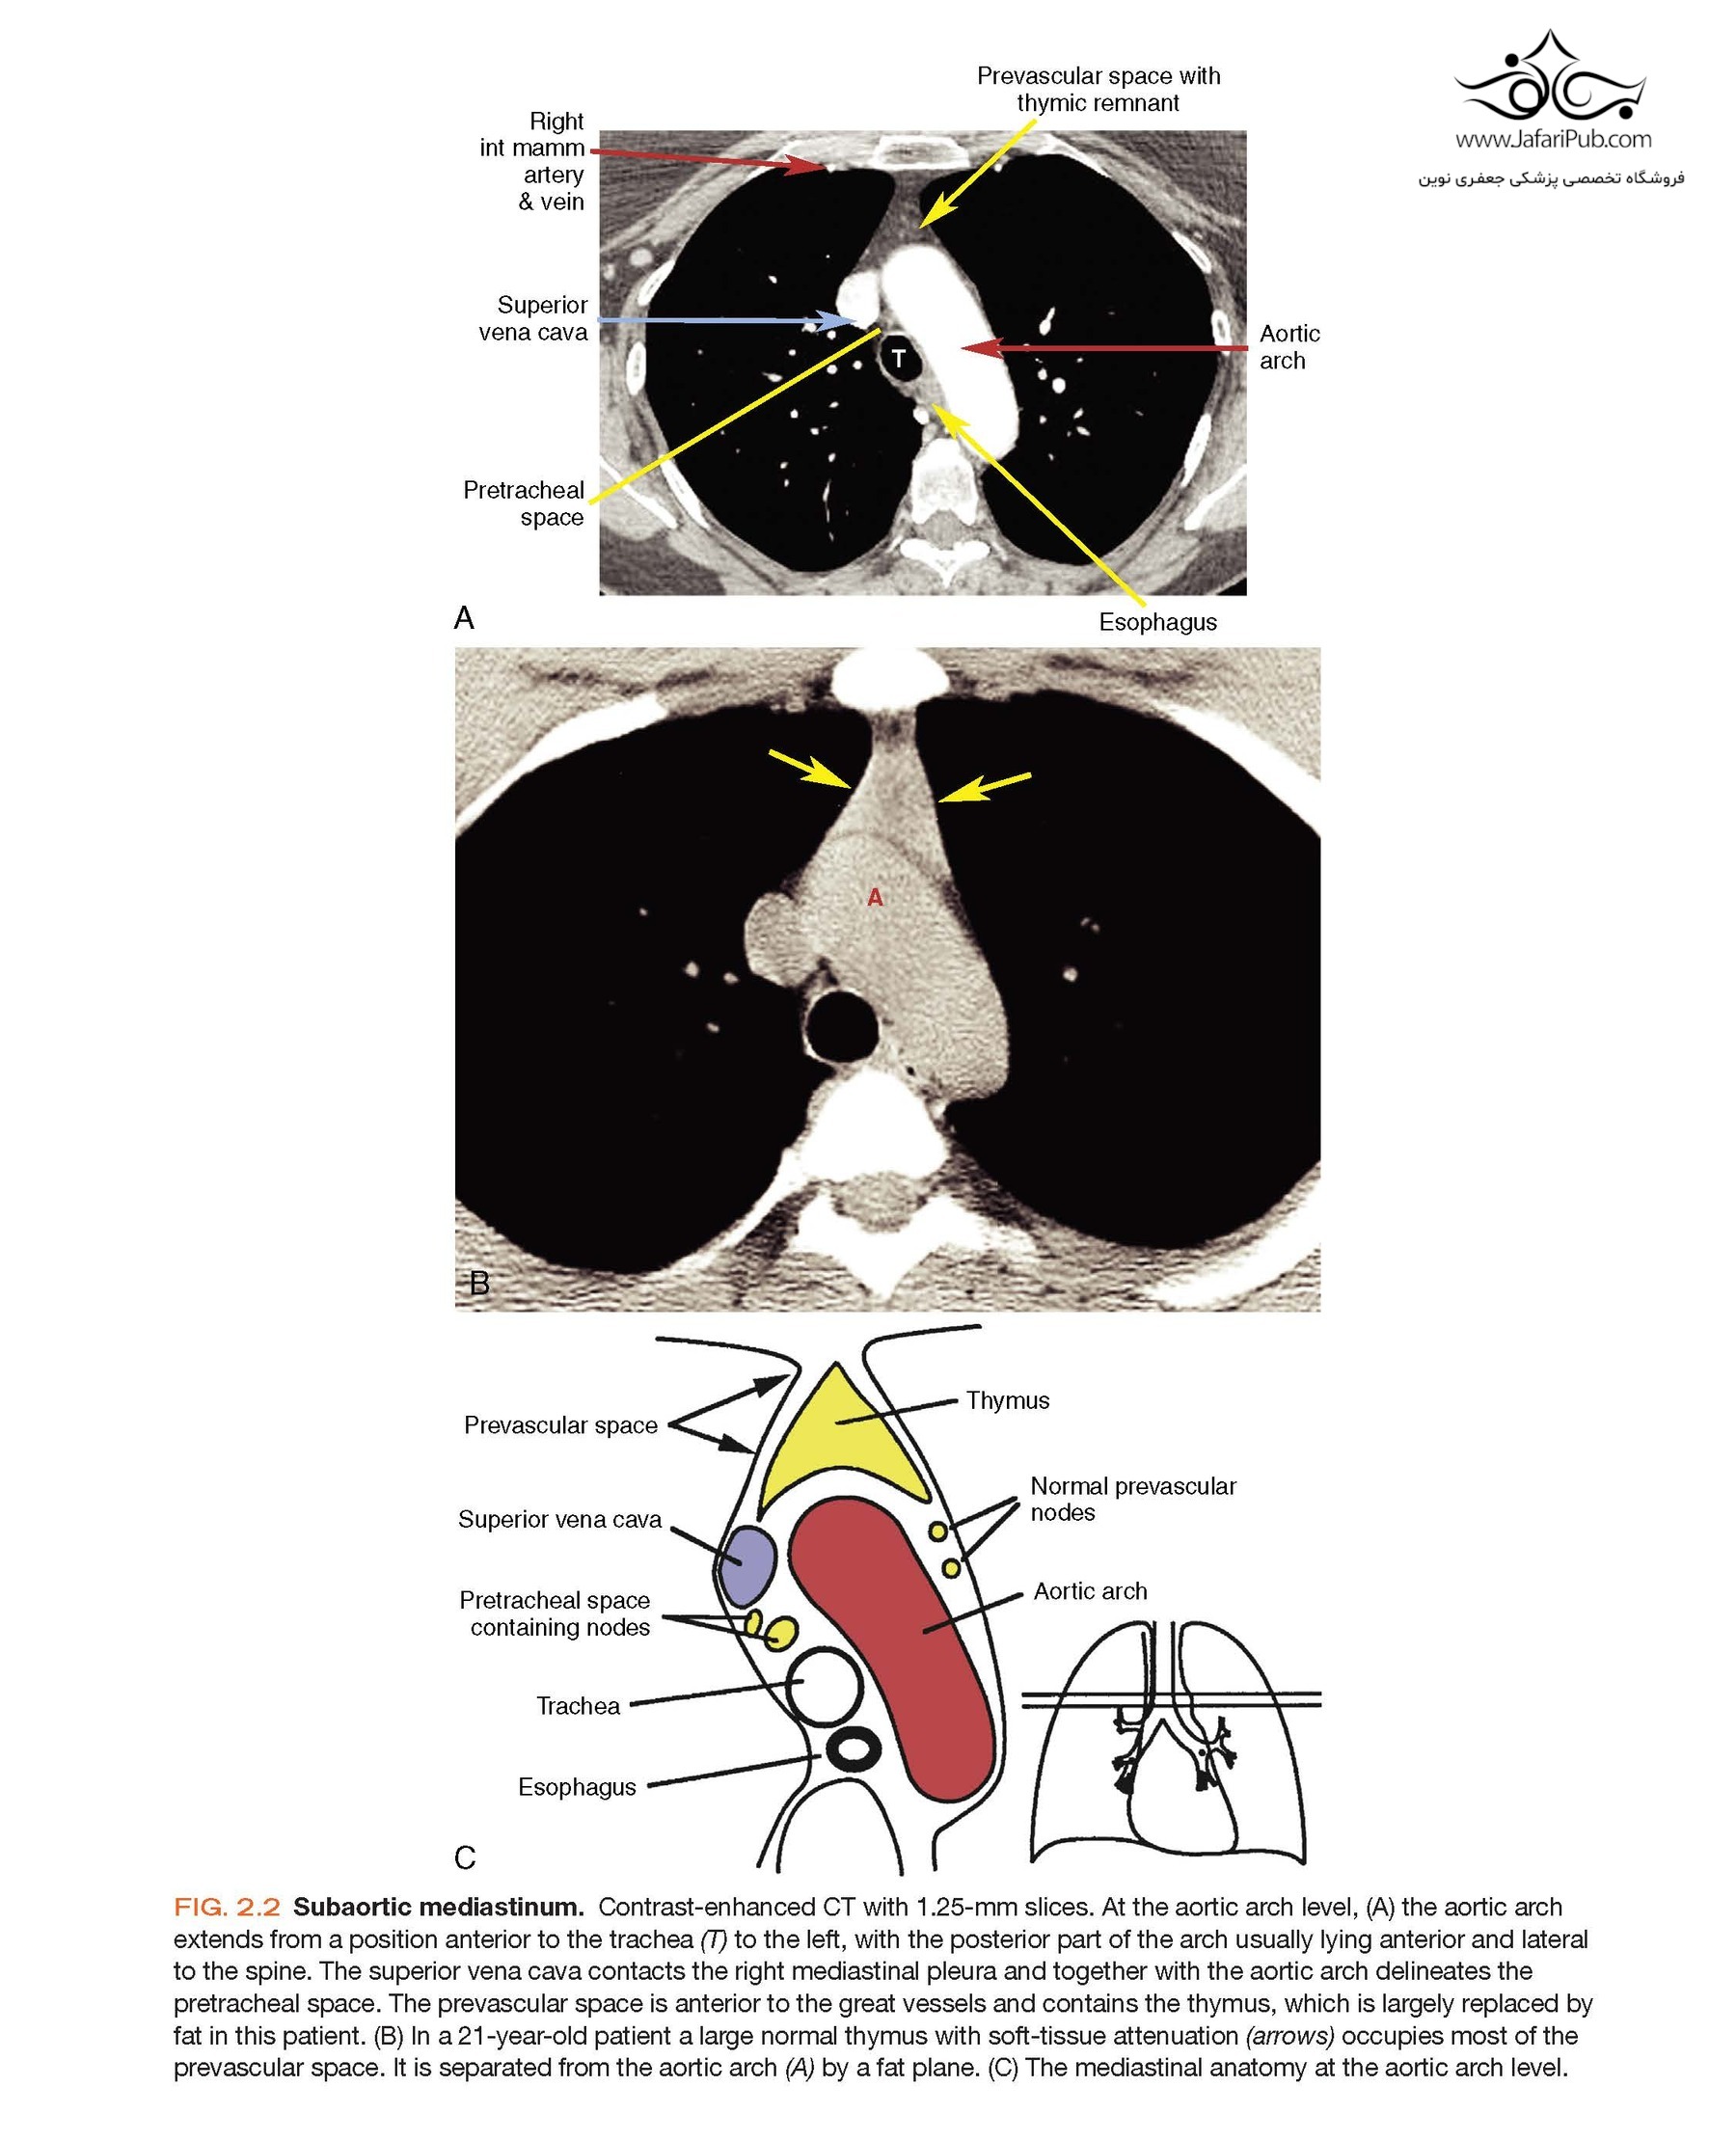

Features many new topics, discussions of additional diseases, and new, high-quality images from cover to cover, including updated descriptions and illustrations of normal anatomy and incidental findings.